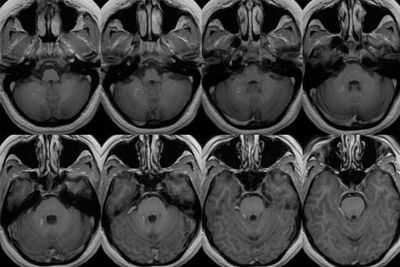

Сосудистая мальформация на МРТ